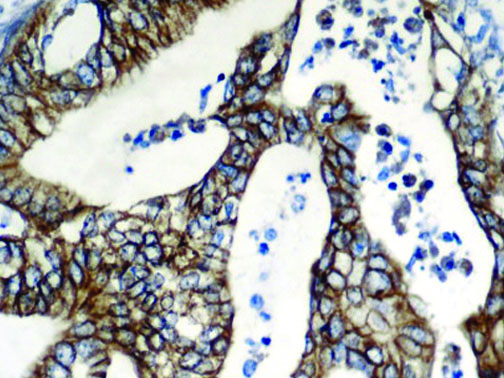

The first cytokines released are interleukin 1β (IL-1β) and tumor necrosis factor-α (TNF-α), which attract a variety of circulating white blood cells (WBCs) to the infection site, including neutrophils, monocytes, macrophages, and natural killer (NK) cells. This response, along with the antipathogenic chemicals released by these cells (i.e., complement), comprise the innate immune response. These cells directly attack the invading pathogen and also release additional cytokines, chief among them interleukin-1 and 6 (IL-6). IL-6 is essential for invoking the adaptive immune response, which calls T-cells, B-cells, and T helper (Th) cells to the infection site. IL-6 also stimulates further recruitment, proliferation and activation of macrophages.

This activation induces inflammatory monocytes to highly express IL-6, starting a localized and then systemic cascade effect that results in hyperproduction of IL-6, which accelerates the inflammatory process. Because IL-6 also increases vascular permeability, excessive levels cause blood vessels to become very leaky. This, along with clotting factors released from vascular endothelial cells, stimulates the coagulation cascade, resulting in microthrombosis (tiny clots), which leads to ischemia and tissue death of the kidney, intestines, heart, liver, brain and extremities.